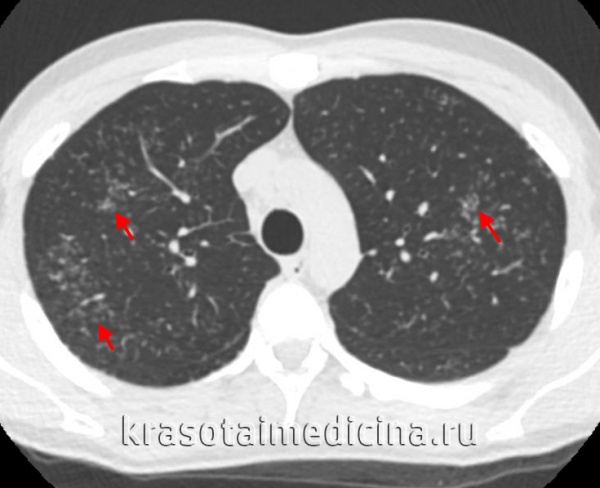

КТ органов грудной клетки. Множественные типичные саркоидозные очаги субмиллиметрового диапазона с диффузным распространением

При проведении бронхоскопии с биопсией могут обнаруживаться косвенные и прямые признаки саркоидоза: расширение сосудов в устьях долевых бронхов, признаки увеличения лимфоузлов в зоне бифуркации, деформирующий или атрофический бронхит, саркоидные поражения слизистой оболочки бронхов в виде бляшек, бугорков и бородавчатых разрастаний. Наиболее информативным методом диагностики саркоидоза служит гистологическое исследование биоптата, полученного при бронхоскопии, медиастиноскопии, прескаленной биопсии, трансторакальной пункции, открытой биопсии легких. Морфологически в биоптате определяются элементы эпителиоидной гранулемы без некроза и признаков перифокального воспаления.